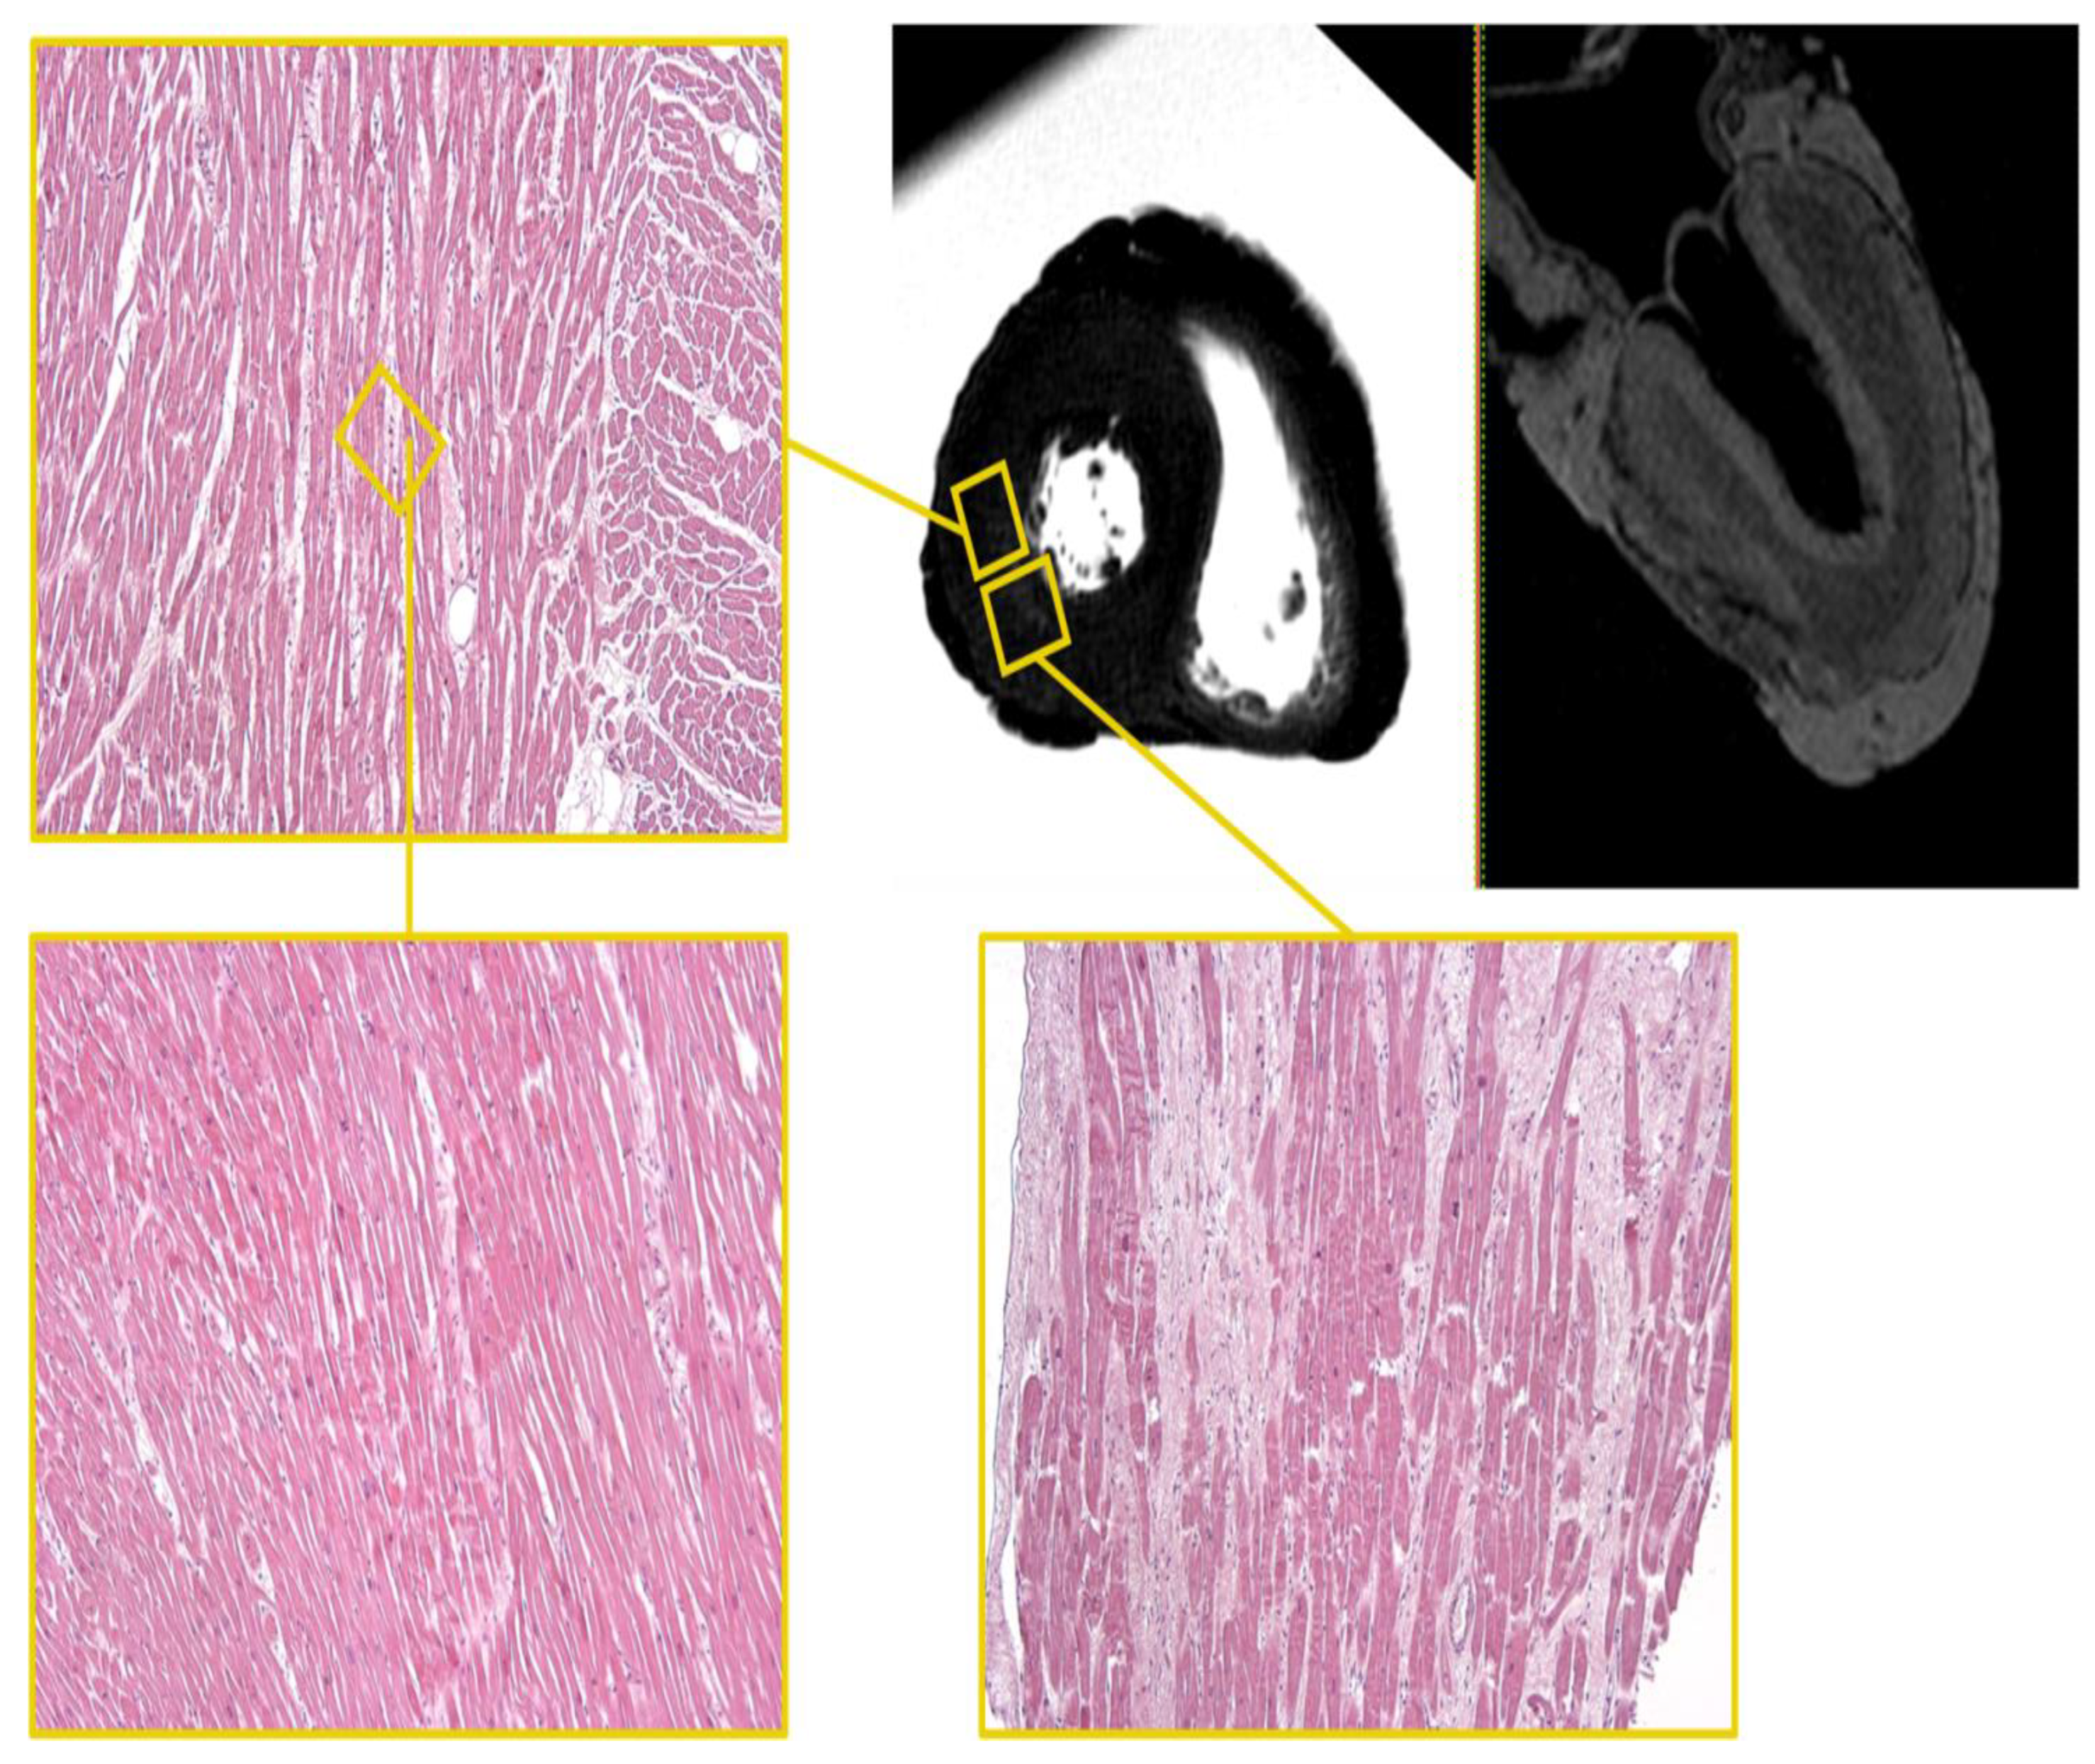

3.1.4. Heart E

PMCMR

Besides abundant epicardial adipose tissue, the heart appeared globally hypertrophic, with an average LV diameter of about 18.35 mm. The RV also looked thickened.

An area of altered signal, with indistinct margins and hyperintense in the STIR sequence, was appreciated in the mid-cardiac area at the sub-endocardial level of the LV postero-lateral site, referable to clinical edema/hypercellularity (Figure 7). Another large area of analogous altered signal, in the same sequence, was evident at the level of the middle third of the septum.

Figure 7.

Heart E. STIR—T1-3D sequences. Hyperintense area in the STIR sequence with indistinct margins in the mid-cardiac area at the sub-endocardial level of the LV posterolateral wall and the corresponding histological H&E samples (×60). Foci of myocells characterized by sarcorexis, with transverse hypereosinophilic bands and contiguous stretched fibers, separated from each other by the presence of amorphous eosinophilic material is present in the interstitial space together with predominantly leucocytic cells. Areas of patchy fibrosis affect the left ventricular wall (white areas).

In the T2-FFE sequences, a global reduction of the myocardial signal was documented; this in-homogeneously hypointense finding was more accentuated at the level of the LV lateral and posterior walls in the mid-basal cardiac region (Figure 7).

At the lateral wall of the left ventricle, the fibers appeared separated by amorphous eosinophilic material, as well as interested by the recurrence of foci of myocardial cells characterized by sarcorexis, with transverse hypereosinophilic bands and contiguous stretched fibers, both in the subepicardial and in the subendocardial area. In particular, the samples were conducted in correspondence with the lateral and posterior walls of the left ventricle. The same findings were found at the middle third of the septum at the same level.